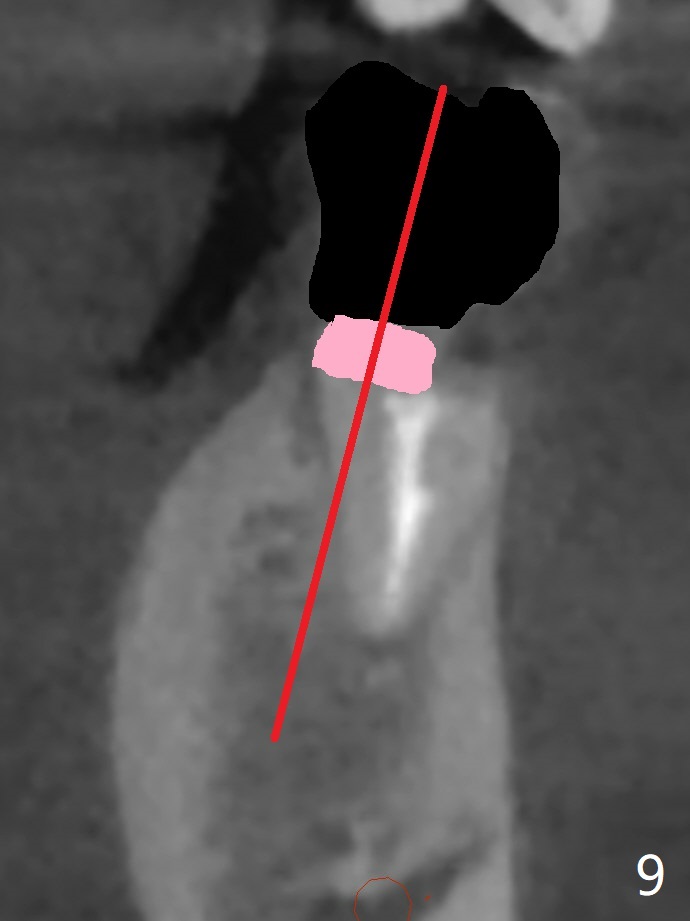

A 40-year-old man with #18 missing and #31 residual roots just fractures the tooth #20 (Fig.1). After discussion, he agrees to have implants at #18 and 20 first. To prevent buccal drifting of osteotomy and implant at #20, the implant will be placed lingual, but it does not contact the lingual plate (Fig.2-4). Traditionally, the whole tooth needs to be extracted (Fig.5,6) before initial osteotomy (Fig.7 red). The latter has tendency to drift buccal because of the lingual slope (Fig.7 arrow). To prevent the drifting, the crown of the tooth is removed (Fig.8). A guide is fabricated with 12 mm offset so that after bone trimmer (Fig.9 pink), the following drills have more contact with metal sleeve. Furthermore the drills will have less chance of buccal shifting because of the presence of the root.